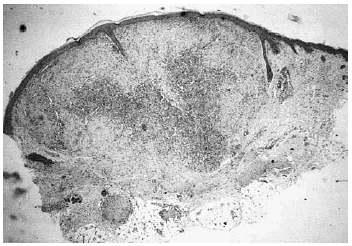

Se realizó biopsia de uno de los tumores que mostró una lesión nodular bien definida, no encapsulada, localizada en la dermis y respetando la epidermis (fig. 2). La parte periférica de la lesión se componía de fascículos compuestos por células fusiformes, de amplio citoplasma eosinófilo y con núcleos alargados. En el centro de la tumoración se encontraban cúmulos de cé-lulas redondeadas o poligonales, con citoplasmas de bordes mal definidos y núcleos hipercromáticos. Esta zona mostraba espacios vasculares con luces interconectadas en un patrón en «asta de ciervo» (fig. 3). La inmunohistoquimia demostró positividad para vimentina y actina específica del músculo. Se practicó hemograma y bioquímica sérica, que fueron normales. La radiografía de tórax, la ecografía abdominal y cardíaca y la tomografía axial computarizada (TAC) cerebral no detectaron anomalías. En la serie ósea se detectaron múltiples imágenes líticas diafisometafisarias en fémures, tibias y húmeros, así como en mandíbula y pelvis, con bordes bien definidos no escleróticos (fig. 4). Se realizó una interconsulta a Neurología solicitando valoración de la parálisis facial, y ésta fue etiquetada de parálisis facial periférica de etiología probablemente obstétrica.

Fig. 2.--Lesión tumoral intradérmica que muestra un patrón bifásico.

Histológicamente la miofibromatosis infantil presenta un patrón bifásico característico2, 15. Suelen aparecer uno o varios nódulos bien definidos, no encapsulados, en dermis o tejido celular subcutáneo. La periferia de cada nódulo se compone de fascículos de células fusiformes, de citoplasma eosinófilo, con núcleos alargados, a veces en cigarro puro, que recuerdan al leiomioma. En cambio, el centro se compone de células menos diferenciadas, poligonales, de núcleos hipercromáticos redondeados u ovales que delimitan espacios vasculares interconectados en un patrón muy similar al del hemangiopericitoma. Ocasionalmente, el patrón histológico se invierte, de forma que la zona similar al hemangiopericitoma se dispone en la periferia y la zona similar al leiomioma es central16. Inmunohistoquímicamente se detecta positividad para actina y vimentina y negatividad para desmina y proteína S-100. Por las características ultraestructurales de las células y el patrón inmunohistoquímico se acepta que es un tumor de estirpe miofibroblástica2. No obstante, otros autores encuentran evidencia de diferenciación hacia músculo liso14 o hacia pericito17. La similitud histológica con el hemangiopericitoma congénito y con el fibrosarcoma congénito puede plantear problemas de diagnóstico diferencial, ya que también tienen semejanzas clínicas y afectan al mismo grupo de edad17. El fibrosarcoma tiene peor pronóstico y es importante distinguirlos, para lo cual puede ser útil realizar estudios citogenéticos. El fibrosarcoma presenta anomalías cromosómicas numéricas, generalmente trisomías, que no aparecen habitualmente en la miofibromatosis18. Con respecto al hemangiopericitoma congénito, se ha propuesto que se trate de una forma de miofibromatosis infantil en la que predomina el patrón histológico similar al hemangiopericitoma19.